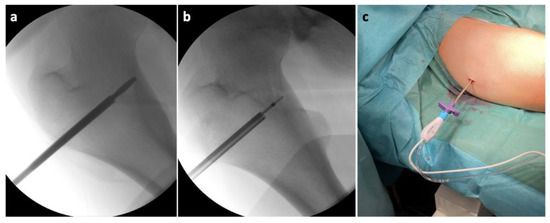

Then, after an additional disruption of the nidus with a drill, we commenced with inserting the RFA probe (Figure 6).

Figure 6.

Intraoperative X-ray of the proximal femur showing: (a) disruption of the nidus with a drill; (b) positioning of the RFA (Radiofrequency abaltion) probe in the nidus; (c) the RFA probe inserted in the working cannula.

We used a 7 mm probe tip heated to 70 °C for 6.5 min. After finishing the ablation program, we extracted the probe with the working cannula and finished the procedure with two absorbable stitches of the skin (Figure 7).